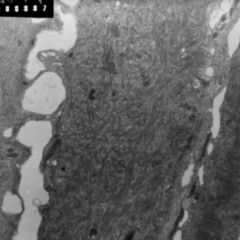

Als Intrazellularraum (IZR) wird in der Pharmakologie der Verteilungsraum innerhalb des menschlichen Organismus bezeichnet, der aus der Gesamtheit aller von Zellmembranen umschlossenen Zellbestandteile gebildet wird und daher also vor allem aus den Zellorganellen, der Zellflüssigkeit und unterschiedlichen Einschlüssen besteht. Es handelt sich beim IZR weder um einen zusammenhängenden, noch – wegen ständiger Austausch- und Umbauprozesse – um einen eindeutig abgegrenzten Raum, sondern um eine modellhafte Auffassung, die in der Pharmakokinetik praktische Bedeutung hat.